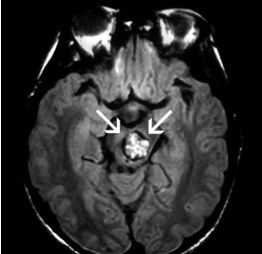

腦部海綿狀血管瘤(Cavernomas)(見圖一)是屬於腦血管畸形的其中一種類型,形狀就像一個 「桑子果」(見圖二),多生於微細的血管上,這血管瘤多為良性,屬於較常見的一種先天性腦部血管瘤,多發生在小腦,偶見於腦幹或脊髓。

圖一